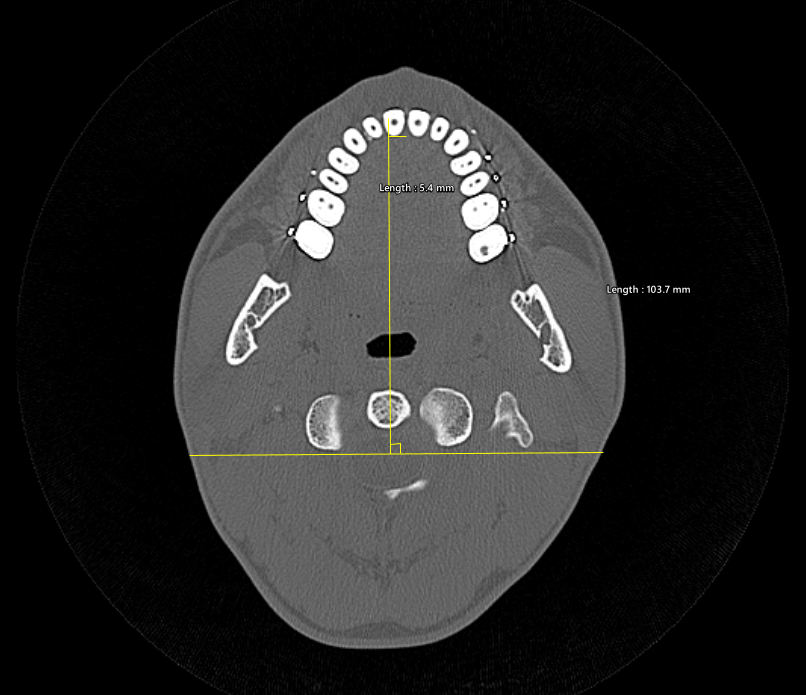

kirgovd Опубликовано 2 часа назад Поделиться Опубликовано 2 часа назад (изменено) При анализе неполного КЛКТ (нижней челюсти не было) выявил смещение центра верхнего зубного ряда вправо на 5.4 мм относительно срединной линии (примерно построена по точкам середины глазниц и затылочного выступа). Ротации максиллы (Yaw) не заметил, верхняя треть лица симметрична. Считается ли это клинической нормой? Планирую сделать полное КЛКТ, чтобы было видно общую картину, но что можно сказать по этому срезу? Изменено 2 часа назад пользователем kirgovd Ссылка на комментарий

kirgovd Опубликовано 19 минут назад Автор Поделиться Опубликовано 19 минут назад (изменено) по сошнику примерно так же, а по гребню 7.1 Изменено 12 минут назад пользователем kirgovd Ссылка на комментарий